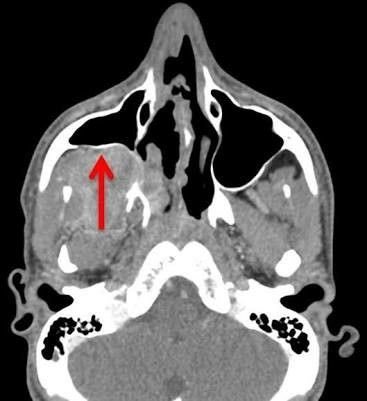

DX?

Syndromic association?

Hollman miller sign: Anterior bowing of the posterior wall of the maxillary sinus that occurs as a result of nasopharyngeal angiofibroma

Can be associated with Gardner’s syndrome